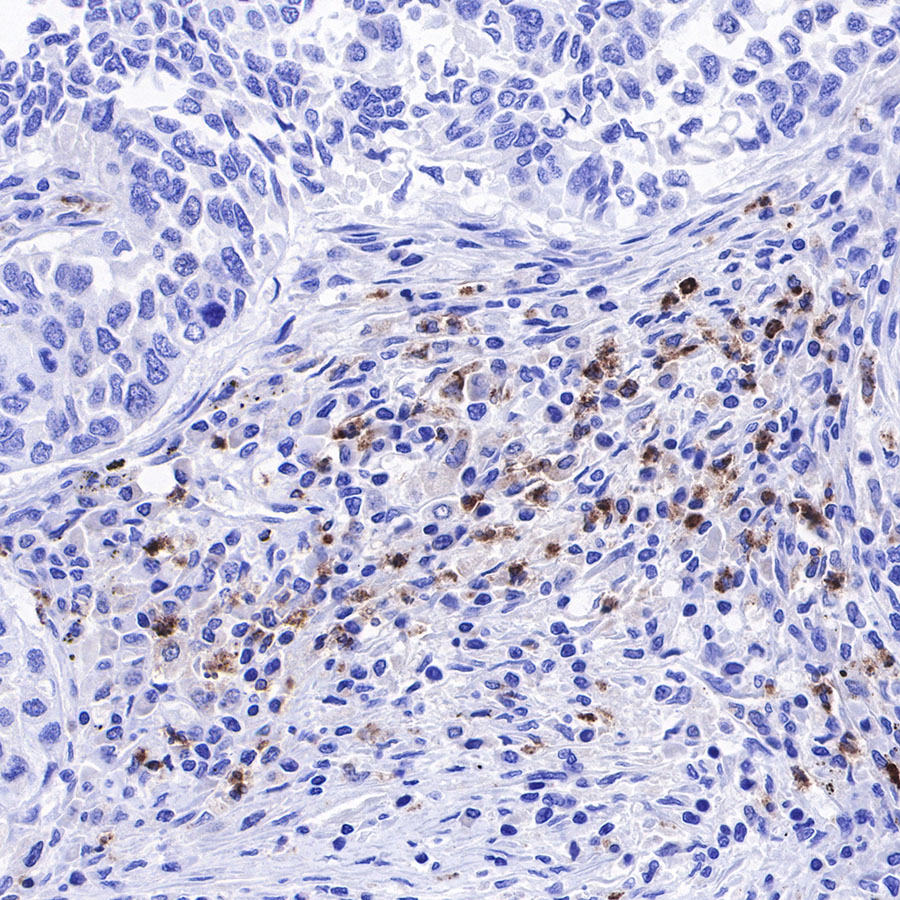

Immunohistochemistry

IHC shows positive staining in paraffin-embedded human spleen. Anti-Lysozyme antibody was used at 1/100 dilution, followed by a HRP Polymer for Mouse & Rabbit IgG (ready to use). Counterstained with hematoxylin. Heat mediated antigen retrieval with Tris/EDTA buffer pH9.0 was performed before commencing with IHC staining protocol.